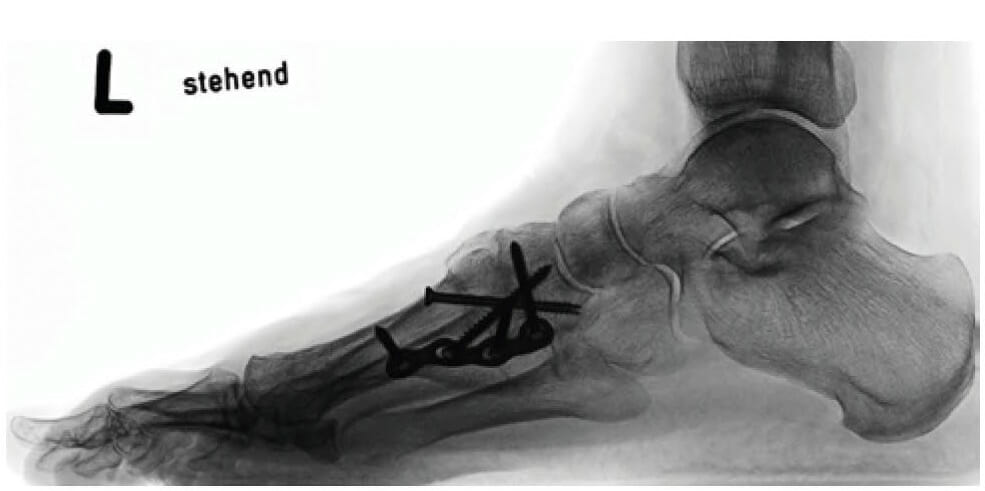

Operative Therapie modifiziert nach Lapidus

Bei ausgeprägten Fehlstellungen mit sehr großen Winkeln zwischen M1 und M2 sowie übermäßiger Mobilität der Mittelfußknochen zueinander und im Übergang von Mittelfuß zu Fußwurzel wählen wir diese Versorgung.

Hier erfolgen zusätzlich differenzierte Eingriffe an den Weich-teilen (Sesambeine, Gelenkkapsel, Muskelansätze), um das Großzehengrundgelenk wieder normal auszurichten. Dann erfolgt korrigierende Versteifung von Gelenken am Übergang Fußwurzel zu Mittelfuß. Hiermit gewinnt der Fuß wieder seine verloren gegangene Stabilität des 1. und 2. Strahles. Alle Zehengelenke bleiben beweglich.

Für die Stabilisierung (Arthrodese) werden die Gelenkflächen der zu beweglichen oder falsch ausgerichteten Gelenke entfernt. Dies sind die Gelenke zwischen M1 und C1, C1 und C2 sowie basisnah M1 und M2. Gelegentlich auch C2 und C3. Die Gelenkflächen werden in optimierter Ausrichtung des Gesamtfußes aufeinander gestellt und z. B. durch eine Kombi-nation aus Schrauben und Platten stabil verbunden (Plantare Lapidusplatte).

Dabei wird die notwendige Ausrichtung des Fußes am zentralen 2. Strahl wiederhergestellt.

Hier kann in speziellen Fällen teilweise mit resorbier-baren Implantaten gearbeitet werden.

Auch hier ist die Versorgung der Gelenkkapsel des Großzehengrundglieds inklusive Rezentrierung der Sesambeine wichtig.